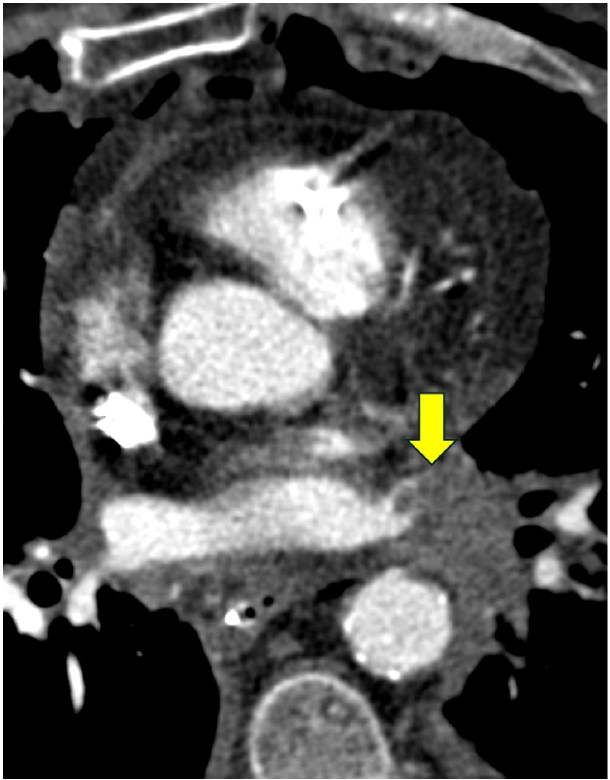

Pulmonary vein thrombosis and pulmonary venous anastomotic stenosis occur during the immediate and early postoperative periods, usually within 48 hours of lung transplant [8]. In pulmonary vein thrombosis, CT of the chest with IV contrast material shows a filling defect within a pulmonary vein, which may or may not be accompanied by consolidation, ground-glass opacities, and septal-line thickening in the lung parenchyma drained by the thrombosed pulmonary vein; the airspace opacities and septal-line thickening represent edema and hemorrhage due to venous ischemia and infarction. Endovascular intervention can be attempted, but cases of severe pulmonary vein thrombosis require surgery. Figure 7 (left) shows a patient with pulmonary vein thrombosis.